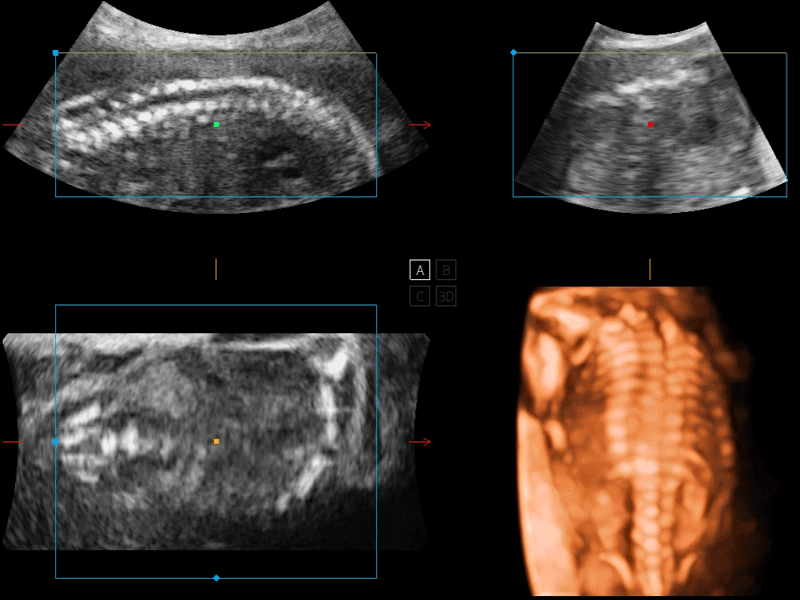

S-Live 高分辨率容积成像

通过仿真成像技术对3D/4D立体数据进行渲染,多种初始光源位置可选,并支持轨迹球360°光源位置自由调节,清晰显示不同方位容积图像细节。

S-Fetus 产科扫查助手

S-Fetus基于大数据深度学习算法,能够帮助您在产前筛查过程中智能识别胎儿标准切面、自动测量并录入报告。一个按键,即可智能、精准、高效地获取胎儿生理指标,极大简化您的产科检查操作。